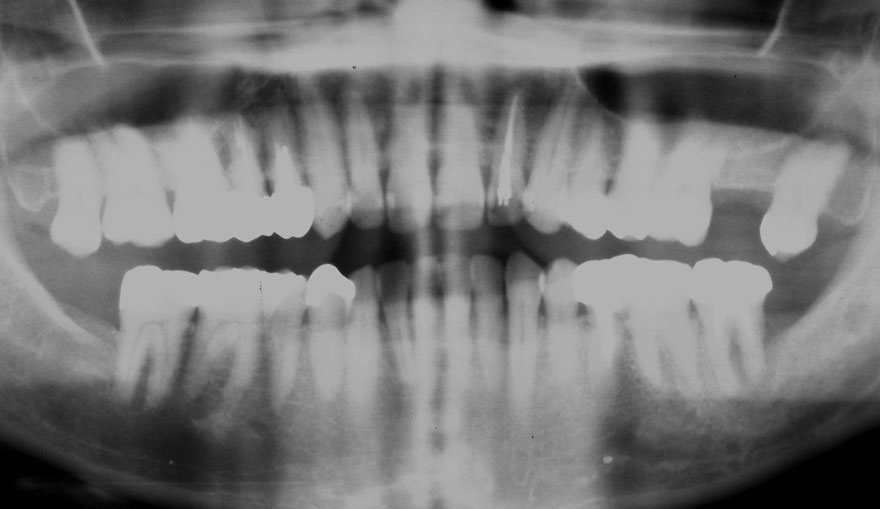

初診時 25歳 女性 平均歯槽骨喪失量:1.11mm

河田歯科医院

22年後 47歳

平均歯槽骨喪失量:1.31mm

22年間喪失量:-0.19mm

年間喪失速度:-0.009mm

(ケア頻度:2.35ヵ月ごと)